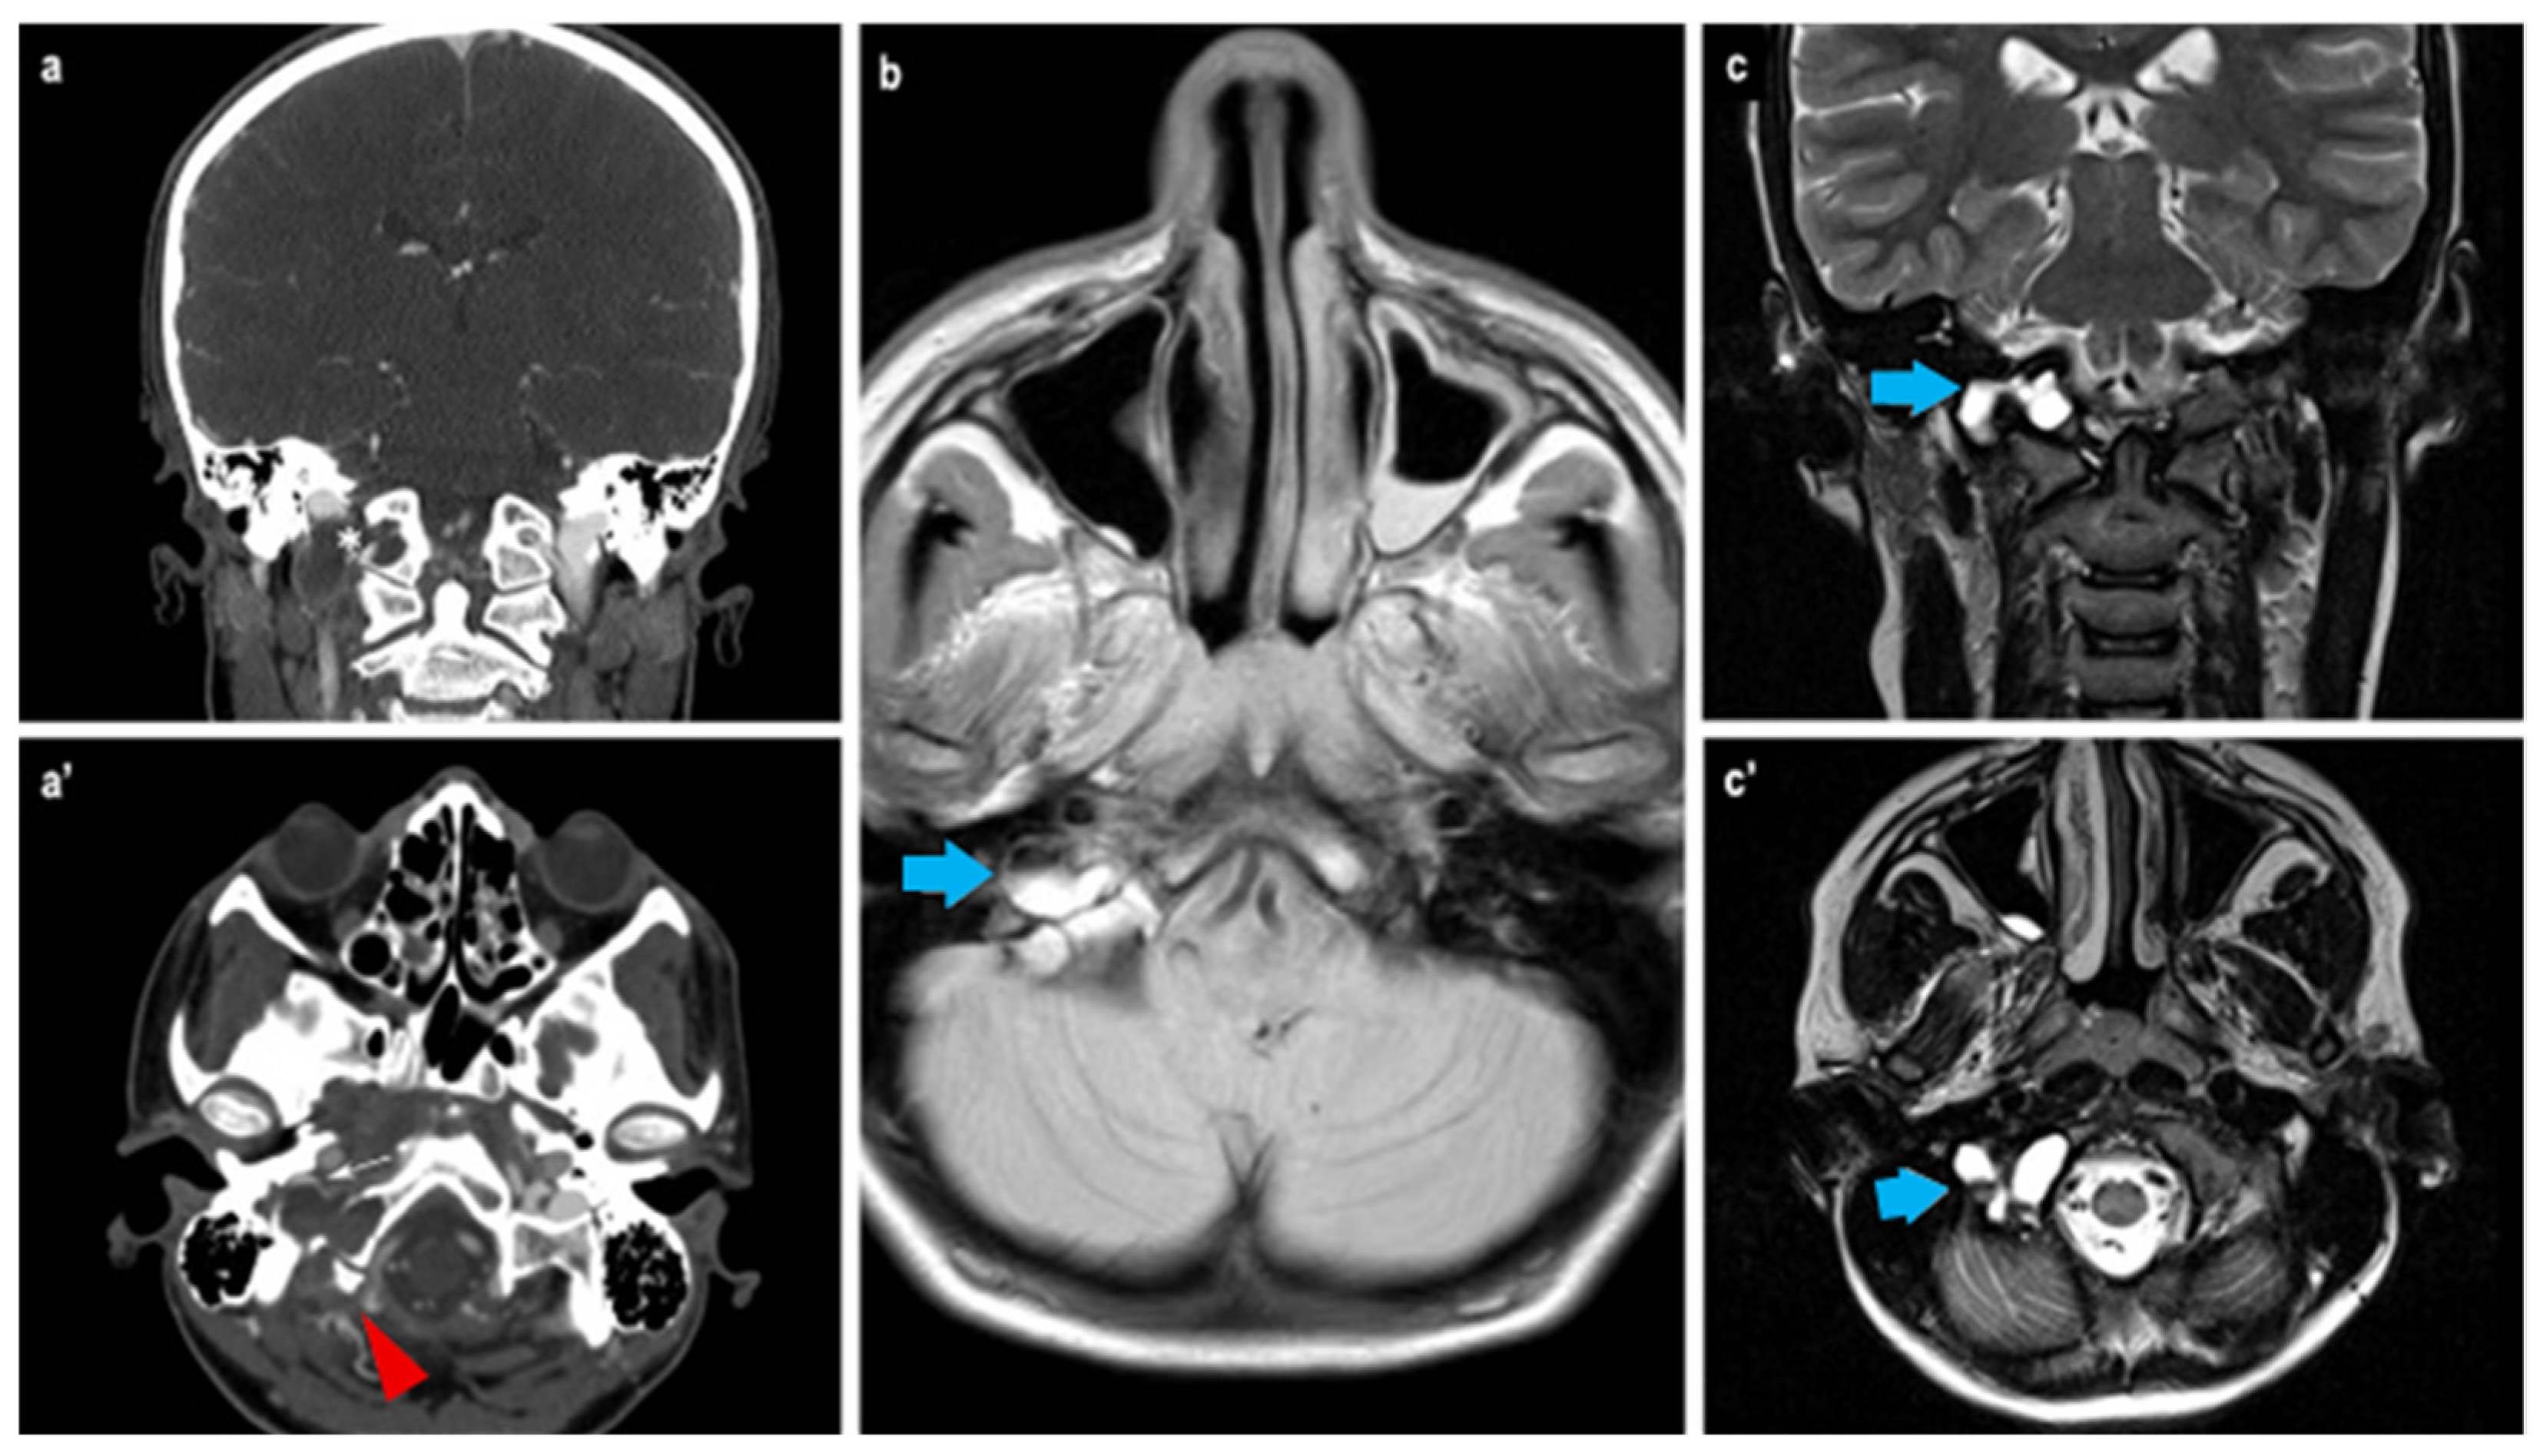

3. Case Report

Our case report | 2025 | Italy | 1 | 14 | M | Occipital condyle | Headache, dizziness, impaired vision, and fall | No | No | Resection | 1 yr |